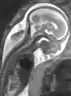

Fetal therapy

Fetal therapy, or fetal treatment, is part of fetal medicine. It includes interventions performed on a “sick” fetus with the aim of achieving fetal well being. These interventions include medical (i.e. non-invasive) and surgical procedures. In general a medical intervention is performed by administering medication to the mother. The drug crosses through the placenta and reaches the blood circulation of the fetus. Surgical intervention on the fetus may involve either a direct operation of the fetus or an intervention on the placenta, as in the case of twin-twin-transfusion syndrome (TTTS). In some cases, it may be performed at the time of delivery: the Ex Utero-Intrapartum (“EXIT procedure”) procedure.